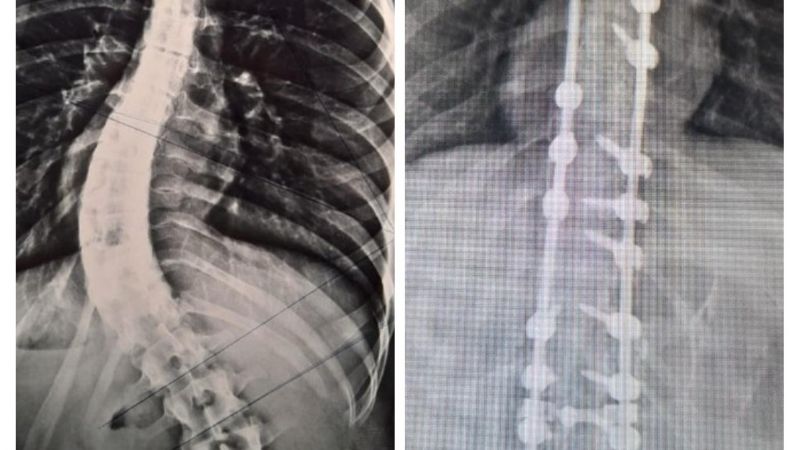

En el Hospital Interzonal San Juan Bautista, de manera exitosa, se realizó días atrás una nueva cirugía para corrección de columna vertebral en una joven paciente que presentaba escoliosis dorsolumbar grave.

En un abordaje integral y colaborativo entre los hospitales San Juan Bautista y el de Niños Eva Perón, un especializado equipo traumatológico, dio intervención a una paciente de 17 años con malformación congénita, que había iniciado su tratamiento en el nosocomio infantil y que finalmente pudo ser operada en el de atención adulta.

En la cirugía, que tuvo una duración de más de 4 horas de quirófano, se logró la reducción de la deformación dorsolumbar mediante la colocación de barras y tornillos pediculares. Los Traumatólogos que estuvieron a cargo fueron Nicolás Flores Kanter y Pablo Ovejero -este último en colaboración por parte del Hospital de Niños-; con la anestesista, Dra. Adriana Bustos, y los instrumentadores Aldo Espilocin y Claudia Sánchez.